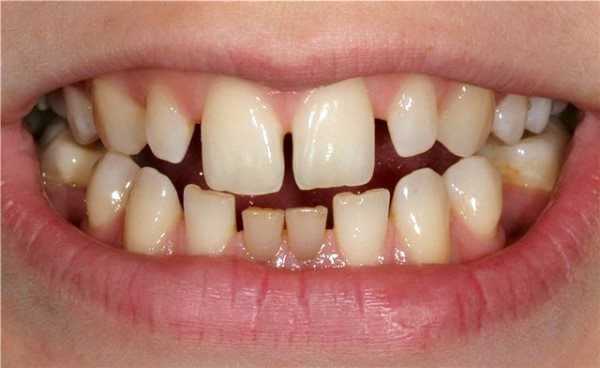

Все формы диастемы представляют собой дефект зубного ряда, выраженный в той или иной степени. Однако некоторые обладатели диастемы склонны считать ее не эстетическим недостатком, а скорее некой «изюминкой» внешности и не видят необходимости в стоматологической помощи.

Тем не менее, межзубная щель между центральными резцами редко бывает относительно узкой и параллельной. Значительно чаще за счет отклонения центральных резцов она имеет треугольную форму с вершиной, обращенной к десне или режущему краю зубов. Кроме этого, диастеме часто сопутствует мощная уздечка верхней губы, волокна которой прикрепляются к гребню альвеолярного отростка и вплетаются в резцовый сосочек, а также зубные аномалии (тремы, микродентия, адентия, поворот резцов по оси), неправильный прикус (дистальный, мезиальный, открытый, глубокий, перекрестный). Поэтому многие люди с диастемой испытывают психологический и физический дискомфорт, стесняются своей внешности и улыбки. Наличие диастемы благоприятствует развитию пародонтита в области фронтальных зубов.

Диастему видно, когда человек разговаривает или улыбается. Основной симптом — промежуток между двумя соседними зубами, ширина которого варьируется от 1-2 мм до 1 см. С точки зрения медицины, диастема является дефектом зубного ряда, однако некоторые люди считают её изюминкой и отличительной особенностью внешности.

Чаще всего у щели треугольная форма, что обусловлено отклонением центральных резцов. Вершина треугольника направлена к десне, а основание — к режущему краю зубов.

К сопутствующим симптомам диастемы относятся:

- Увеличенная губная уздечка. любого типа: перекрёстный, дистальный, глубокий, мезиальный.

- Сопутствующие зубные аномалии: поворот резцов вокруг своей оси, тремы ( промежутки не только между резцами, но и другими зубами ), микродентия, отсутствие одного или нескольких зубов.

Из-за этих отклонений люди с диастемой часто испытывают физический и психологический дискомфорт, страдают от комплексов, связанных с внешностью и низкой самооценкой.